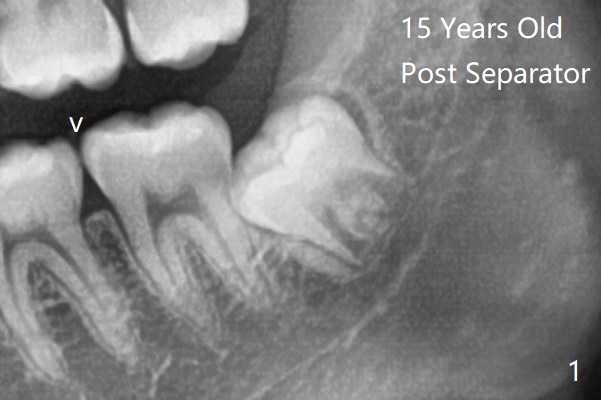

1.5年智齿牙根长长(图二)。1.5月后下颌智齿拔除放置Osteogen Plug(图三)。